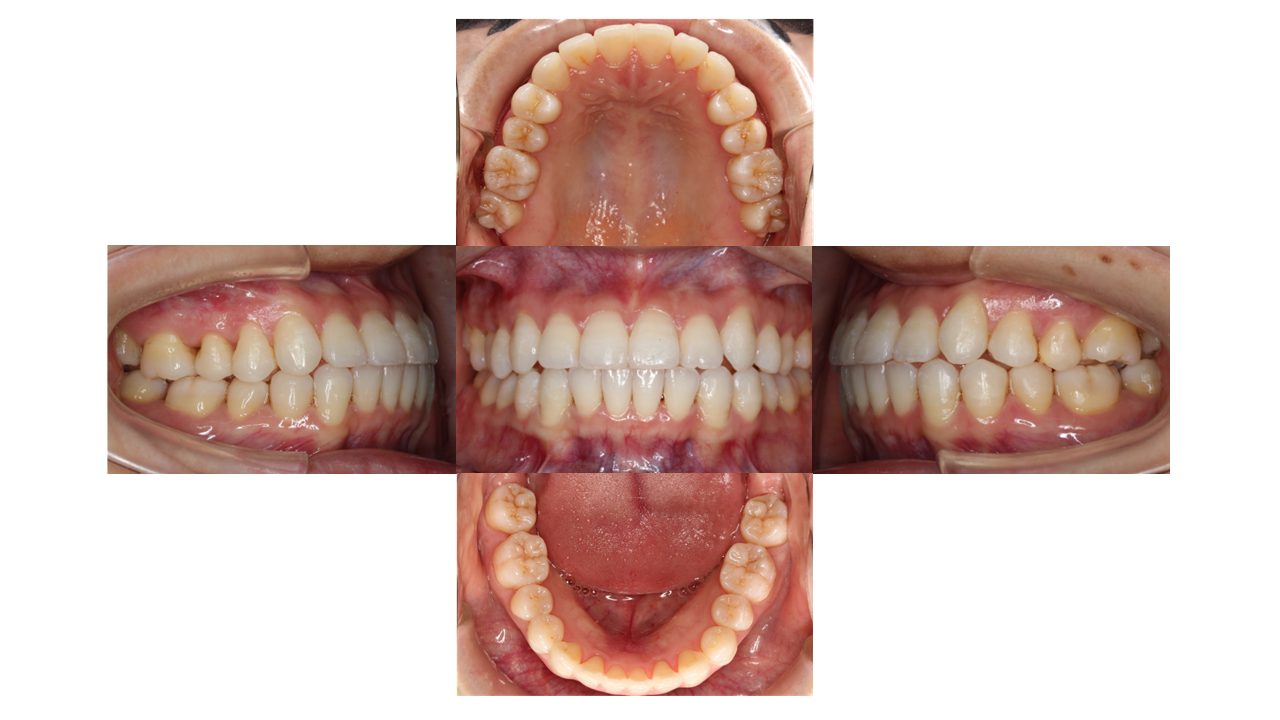

1年8カ月経過の口腔内の状態です。

全体的な凸凹が改善し、ご満足いただけました。